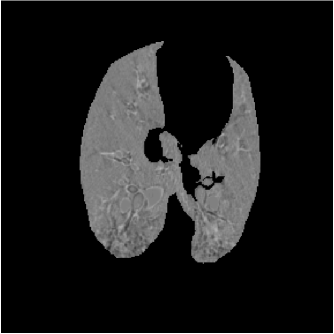

For each animal, approximately 200 automatically identified landmarks within the lungs are used to compute registration accuracy. The landmarks are widely distributed throughout the lung regions. Figure 5 shows an example of the distribution of the landmarks in animal D for both the and images. The coordinate of each landmark location is recorded for each image data set before and after registration for all four animals. Figure 6 shows the landmark distance before and after registration for four animals. The grey boxes show the magnitude of respiratory motion during the tidal breathing. For all four animals, before registration, the average landmark distance is 6.6 mm with a minimum distance of 1.0 mm, maximum distance of 14.6 mm, and standard deviation of 2.42 mm. After registration, the average landmark distance is 0.4 mm with a minimum distance of 0.1 mm, a maximum distance of 1.6 mm, and a standard deviation 0.29 mm. The trends for all animals are consistent and the results demonstrate that the registrations produced good anatomic correspondences. All registrations were examined and it was confirmed that all Jacobian values had positive values.

Figure 5(a) shows the location of the (Xe-CT) slab overlaid on the image. Figure 7 shows an example of the image registration result from the image to the image. The first row shows the misalignment between the images before image registration. Though the images were acquired without moving the animal between the scans, there is still non-rigid deformation between scans as shown in Fig 7(d), as the black and white regions represent the large intensity difference between Fig. 7(a) and (b). In addition, the slice thicknesses were quite different which causes partial volume artifacts. After image registration, the image is aligned to the image, and the resulting difference image (shown in Fig. 7(e)) is near zero. The transformation from the to the image allows us to map the Xe-CT sV into the coordinate system of image. Note that since the regions outside the lung are not included in the registration process, the mediastinum and other body tissues are not aligned. Also note that the dorsal region of the lung shows a intensity difference after registration. This is due mainly to the gradual progression of atelectasis and tissue edema during the course of the experiment.